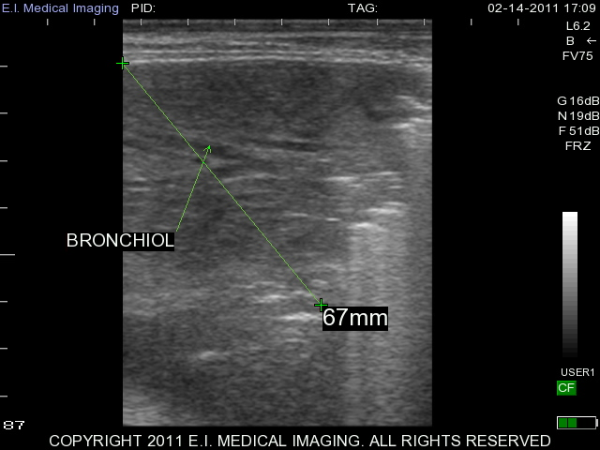

My name is Elizabeth Adams and I am a dairy practitioner in the central valley of California. Recently, I was able to use the IBEX PRO portable ultrasound to look at calf lungs for evidence of damage from calfhood pneumonia. In veterinary school, I scanned all of my patients with respiratory symptoms because it is a fast, non-invasive exam that provides a lot of information quickly. With ultrasound I can see healthy lungs, pleural effusion, atelectasis, consolidation and abscessation.

Ultrasound allows me to look at the surface of the lung; in a healthy lung, this is all we can see as the lung is full of air and doing its job. In a diseased lung, the surface of the lung is abnormal and allows penetration of the ultrasound waves deep into the lung parenchyma. Young calves require only the penetration of a 5-7.5MHz rectal ultrasound probe to see the evidence of damage from previous pneumonia.

Thanks to E.I. Medical Imaging's Research Loaner Program, I was able to scan lungs of calves at approximately three months of age. I am giving each calf a lung score based on the extent of lung damage seen on ultrasound. These heifers will then be followed out to their first freshening and I will see how well they perform in their first lactation. My hypothesis is that calves with extensive lung damage will not perform as well as their herdmates with healthy lungs. I plan to use ultrasound to help producers make more informed decisions when choosing calves to add to their herd.